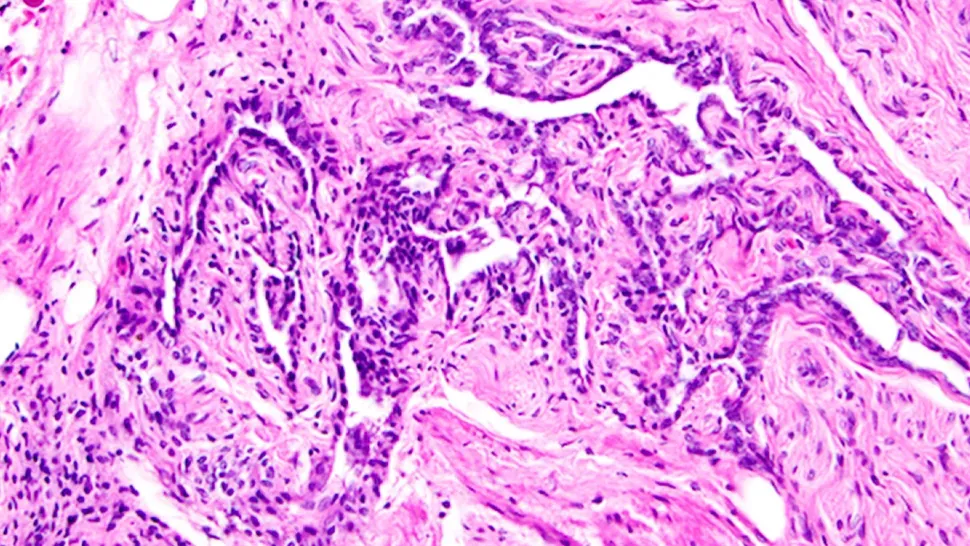

Çalışmada, fareler üzerinde yapılan detaylı analizler, rete ovarii’nin üç ana bölgeden oluştuğunu ortaya koydu:

Kütle spektrometresi analizleri, özellikle EOR’un doğum sırasında binlerce protein içerdiğini ve bu proteinlerin hücreler tarafından üretildiğini gösterdi. Bu proteinler arasında dikkat çeken biri olan IGFBP2, yumurtalık foliküllerinin gelişimini düzenleyen insülin-benzeri büyüme faktörlerini kontrol ettiği düşünülüyor. Ayrıca, floresan boya testiyle gerçekleştirilen deneylerde, EOR’un içindeki sıvının yumurtalığa doğru hareket ettiği gözlemlendi. Bu, rete ovarii’nin yapısal bir rolün yanı sıra, aktif bir hareket ve iletişim ağı olduğunu gösteriyor.

Çalışmanın önemli bir bulgusu, rete ovarii hücrelerinin östrojen ve progesteron gibi hormonlara yanıt verdiği ve bu hormonların reseptörlerini taşıdığıdır. Bu, yapının sadece yapısal değil, aynı zamanda hormonal olarak da aktif olduğunu gösteriyor. Lancaster Üniversitesi’nden anatomi profesörü Adam Taylor ise, rete ovarii’nin yumurtalık çevresindeki sıvıyı kontrol ettiği ve hormonal sinyalleri algılayıp yanıt verdiği görüşünde. Bu yeni bilgiler, rete ovarii’nin vücut genelinden alınan sinyalleri yumurtalığa ileten bir ‘anten’ gibi işlev görebileceğini düşündürüyor.